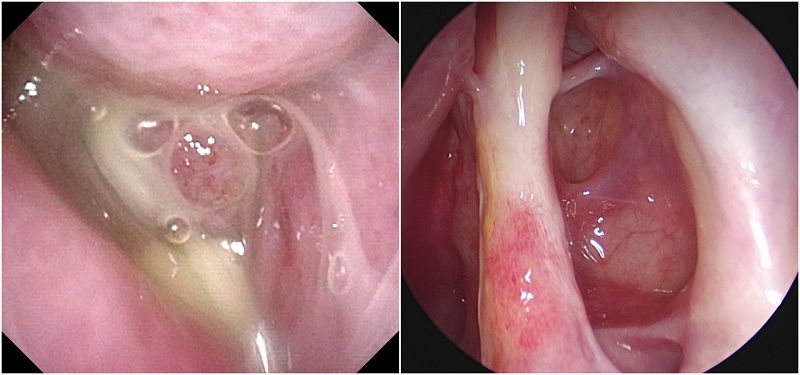

鼻竇炎的診斷除了症狀評估、內視鏡檢查,必要時也會輔以X光確認發炎情況、電腦斷層辨識發炎位置。陳昱安醫師表示,鼻竇炎初期可以以一般感冒藥治療,可是如果變成慢性鼻竇炎、出現嚴重併發症或影響日常生活的情況就需要手術治療。不同於傳統手術必須將發炎鼻竇整個切除,破壞鼻腔構造,「功能性內視鏡鼻竇炎手術」是透過鼻孔的自然孔洞將內視鏡伸入病灶,將腫脹的息肉或病灶切除,擴大鼻竇開口並清除發炎黏液,使鼻竇開口通暢,針對鼻中膈彎曲或結構異常的病人,耳鼻喉科醫師也會同時手術矯正鼻腔構造。一般而言,此類手術初期成功率高達98%,且追蹤到第四年的成功率仍有高達94%,即使是二次手術,只要手術方式得宜,病灶切除完善,也可以達到與首次手術相當的成功率。